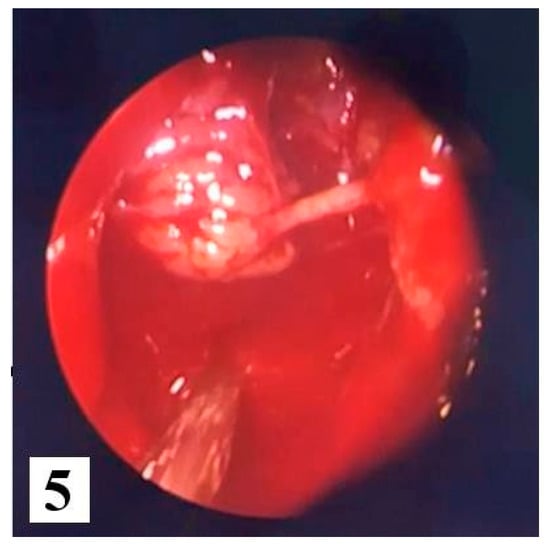

We opted for endoscopic surgical treatment with "piecemeal" type ablation of the papillomatous tumor formation at the level of the right nasal fossa, because the inverted papilloma was classified in stage 2 of the Krouse classification. We resected the tumor from its ethmoidal level (antero-posterior ethmoidectomy) to the jaw level (maxillary antrostomy); a portion of the middle nasal turbinate was also resected to the posterior insertion level where a vascular branch from the sphenopalatine artery was cauterized. Many tissue fragments were taken, including maxillary sinus and ethmoid sinus (suspected origin) bone fragments which were all sent for HP examination. Final endoscopic assessment did not reveal residual tumor remains at the right nasal fossa level (Figure 5 and Figure 6).

Figure 5.

Intraoperative excision of the tumor.